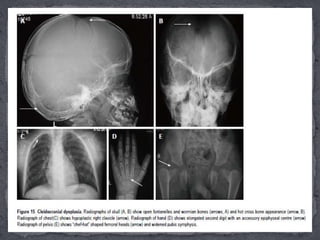

 It isan autosomal dominant dysplasia with predominant membranous bone involvement. Due to its dominant mode of inheritance it can be seen in multiple members of the same family and can present in childhood to as late as 30 years of life.

 Essential radiologicalfeatures:  (1) The skull shows delayed ossification of calvarium, multiple wormian bones, persistently open sutures and fontanelles giving a hot cross bun appearance. However the mandible is normal with maintained angle .  (2) The clavicles are either absent (10%) or hypoplastic (90%), hypoplasia affecting the lateral ends more than middle or medial ends. Also the scapulae may be small and thoracic cage cone-shaped.  (3) In hands and feet, the 2nd digit is elongated due to presence of accessory epiphyses for the second metacarpal while the distal phalanges are small and pointed.  (4) The pelvis is small with widened symphysis pubis and abnormal shape of femoral heads called “chef-hat” appearance.